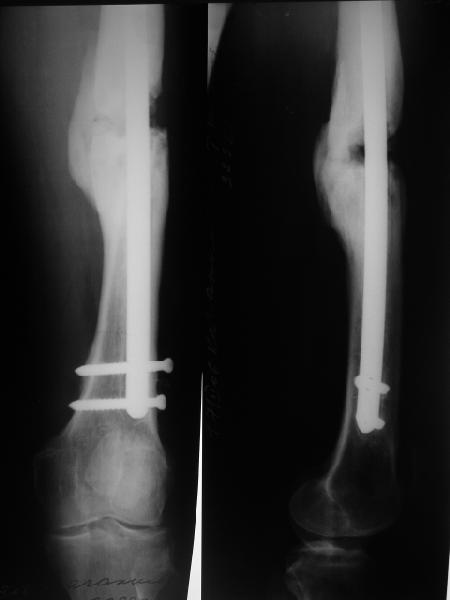

Давайте посмотрим на снимки бедра. В принципе, с наличием "эндопротеза диафиза" в виде мощного интрамедуллярного стержня не надо убиваться с обширными вмешательствами на очаге с кровопотерями, создавать большую площадь контакта, замещать все дефекты. Достаточно образования после дистракции узенького мостика по одной стороне. Со временем он упрочится, стержень в канале будет помогать сохранять длину и ось несколько лет. Даже если не будет смыкания трубок, можно потом стержень отпереть, за счет этого улучшиться контакт. Можно сделать реостеосинтез с рассверливанием стержнем большего диаметра. Важно, что все это время можно нормально пользоваться конечностью.

В приложении снимки бедра - с такой картинкой пациентка ходит, не хромает, работает инженером 3,5 года после операции с первых дней, хотя еще и инсулинозависимый диабет.

У нас есть все же сомнения, насколько он "тугой". Наличие хоть и нестабильной но все же фиксации пластиной, маскирующей степень подвижности; сочетание на рентгенограммах зон гиперостоза с зонами лизиса не дает четкой уверенности ни в том, что это тугой ложный сустав в классическом понимании, ни что это истинно атрофическая ситуация. А чем сейчас можно быть уверенным? Вот потому и одолевают сомнения.